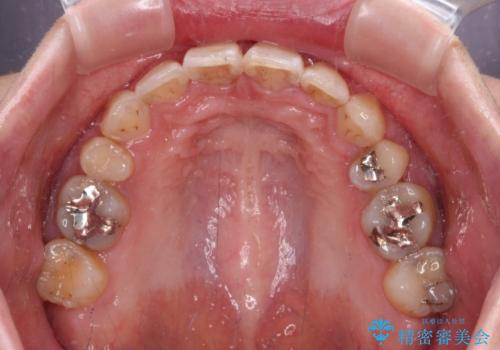

上下前歯の距離が大きかったため、上下の歯が接触するまでに時間がかかりました。

それでも目安である2年半で終えることができ、患者様には大変満足していただけました。